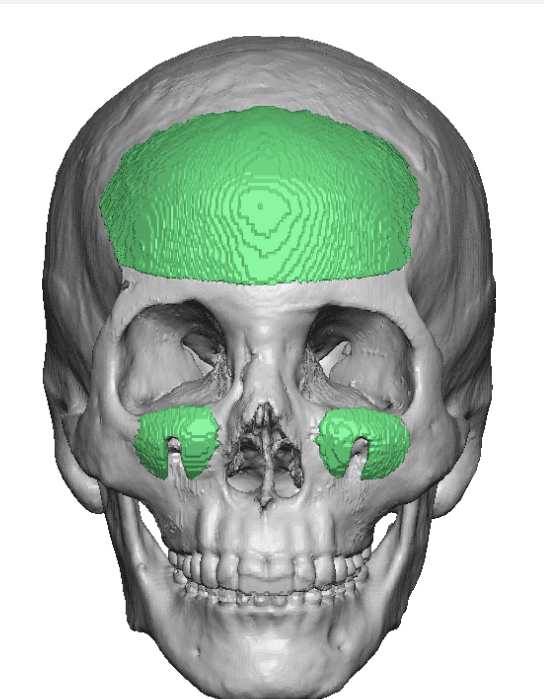

Desire for change of head shape from front view form an inverted V shape to a rounder and wider head shape.

Placement of custom extended forehead-temporal implants through incisions in the crease behind the ear. (he had a prior back of head skull implant which is green in the implant designs and which the head widening implants partially covered it)

Desire for change of head shape from front view form an inverted V shape to a rounder and wider head shape.

Placement of custom extended forehead-temporal implants through incisions in the crease behind the ear. (he had a prior back of head skull implant which is green in the implant designs and which the head widening implants partially covered it)